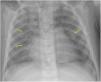

The World Health Organization defines the multisystem inflammatory syndrome in children (MIS-C) as a new syndrome reported in patients aged <19 years old who have a history of exposure to SARS-CoV-2. The onset of this syndrome is characterized by persistent fever that is associated with lethargy, abdominal pain, vomiting and/or diarrhea, and, less frequently, rash and conjunctivitis. The course and severity of the signs and symptoms vary; in some children, MIS-C worsens rapidly and can lead to hypotension, cariogenic shock, or even damage to multiple organs. The characteristic laboratory findings are elevated markers of inflammation and heart dysfunction. The most common radiological findings are cardiomegaly, pleural effusion, signs of heart failure, ascites, and inflammatory changes in the right iliac fossa. In the context of the current COVID-19 pandemic, radiologists need to know the clinical, laboratory, and radiological characteristics of this syndrome to ensure the correct diagnosis.

El síndrome inflamatorio multisistémico pediátrico vinculado a la COVID-19 (SIM-PedS) es, según la Organización Mundial de la Salud, un nuevo síndrome descrito en pacientes menores de 19 años con historia previa de exposición a SARS-CoV-2. La presentación inicial de este síndrome se caracteriza por fiebre persistente que asocia debilidad, dolor abdominal, vómitos y/o diarrea. Menos frecuentemente los pacientes pueden presentar también erupción cutánea y conjuntivitis. El cuadro clínico tiene expresividad y evolución variables, por lo que algunos pacientes pediátricos afectados pueden empeorar rápidamente, desarrollando desde hipotensión y shock cardiogénico a daño multiorgánico. Los hallazgos analíticos característicos del síndrome consisten en elevación de marcadores inflamatorios y disfunción cardíaca. Los hallazgos radiológicos más frecuentes son cardiomegalia, derrame pleural, signos de insuficiencia cardíaca, ascitis y cambios inflamatorios en la fosa ilíaca derecha. En la pandemia actual por COVID-19 es necesario que el radiólogo conozca las características clínico-analíticas y radiológicas de este síndrome para realizar un correcto diagnóstico.